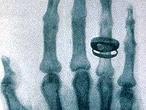

En 1896, el físico Wilhelm Conrad Roentgen había descubierto la relación entre unos extraños rayos catódicos que atravesaban papel y metales y la emulsión fotográfica. Es por esto que se decidió a experimentar con humanos.

Le pidió a su esposa que colocase la mano durante quince minutos sobre la placa de cristal que había creado.Al revelar la misma, apareció una imagen histórica: las falanges de la mano de Berta con su anillo de bodas . Esta fue la primera imagen radiográfica del cuerpo humano y aquí nace la Radiología.